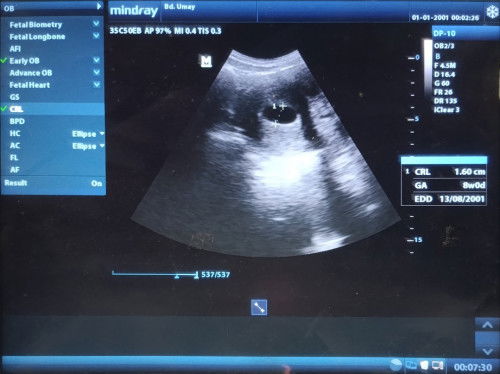

Bunda2 yang baik hati semua... aku mau bertanya bun.. Senin lalu aku USG 2D, tapi kantung kosong... jadi worry bgt, walopun kondisi kantung bagus dll... #SeriusTanya #Sharing_dong_Bund Kalo di kalender hamilkan terhitung 7W, tapi kenapa di USG jadi 8W, itu kenapa yah?